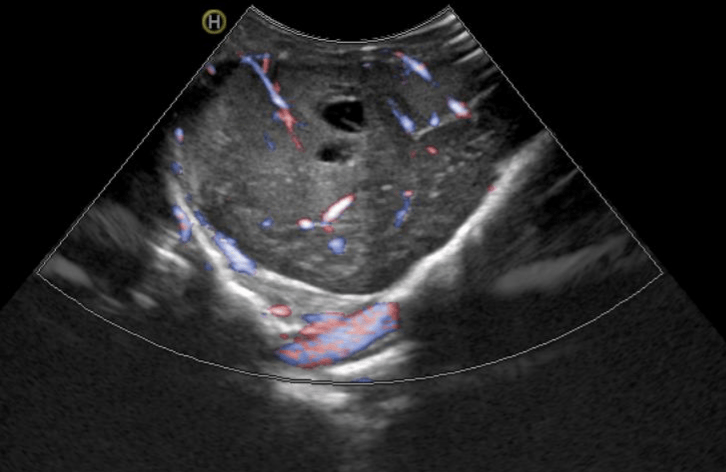

The project aims to analyze intraoperative ultrasound images of glioblastomas and develop new prediction survival models through advanced neuroimaging processing techniques and machine learning algorithms. To collect data, we promoted the creation of the first international database of intraoperative ultrasound images of brain tumors (BraTioUS-DB), in which we will collaborate with at least 6 other hospitals. At the moment we are awaiting the IRB approval of the participating centers, being the first to obtain it the Fondazione Istituto Neurologico Carlo Besta, Milano, Italy. https://www.istituto-besta.it/neurochirurgia

Predicting the survival of patients diagnosed with glioblastoma (GBM) is essential to guide surgical strategies and subsequent adjuvant therapies. Intraoperative ultrasound (ioUS) is a low-cost, versatile technique available in most neurosurgical departments. The images from ioUS contain biological information possibly correlated with the tumor's behavior, aggressiveness, and oncological outcomes. Today's advanced image processing techniques require a large amount of data. Therefore, we propose creating an international database aimed at sharing intraoperative ultrasound images of brain tumors. The acquired data must be processed to extract radiomic or texture characteristics from ioUS images. The rationale is that ultrasound images contain much more information than the human eye can process. Our main objective was to identify a relationship between these imaging characteristics and overall survival (OS) in GBM. The predictive models elaborated from this imaging technique will complement those already based on other sources, such as MRI and genetic and molecular analysis. Predicting survival using an intraoperative imaging technique that is affordable for most hospitals would greatly benefit patient management.